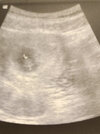

Cześć dziewczyny:) ja już po badaniu! Dziś udałam się na wizytę z PZU i nieco się zdziwiłam jak przyjęła mnie ok. 80 letnia lekarka. Taka kochana babcia heheh w każdym razie po opowiedzeniu mi historii życia oraz wypisaniu skierowania na wiele badań przeszłyśmy do USG. Sprzęt mocno stary wiec szału nie ma ale to co najważniejsze czyli serduszku biło ( chyba 140 ) i wszystko fajnie się rozwija a maleństwo ma 1,17 cm) Nie wiem tez jaki jest wiek ciąży ale wg apki 7t3d, za tydz idę do swojego prywatnego lekarza po więcej info :)

• 135CCA21-FA7C-443B-BD37-77505056C6CD.jpeg

705 KB · Wyświetleń: 122